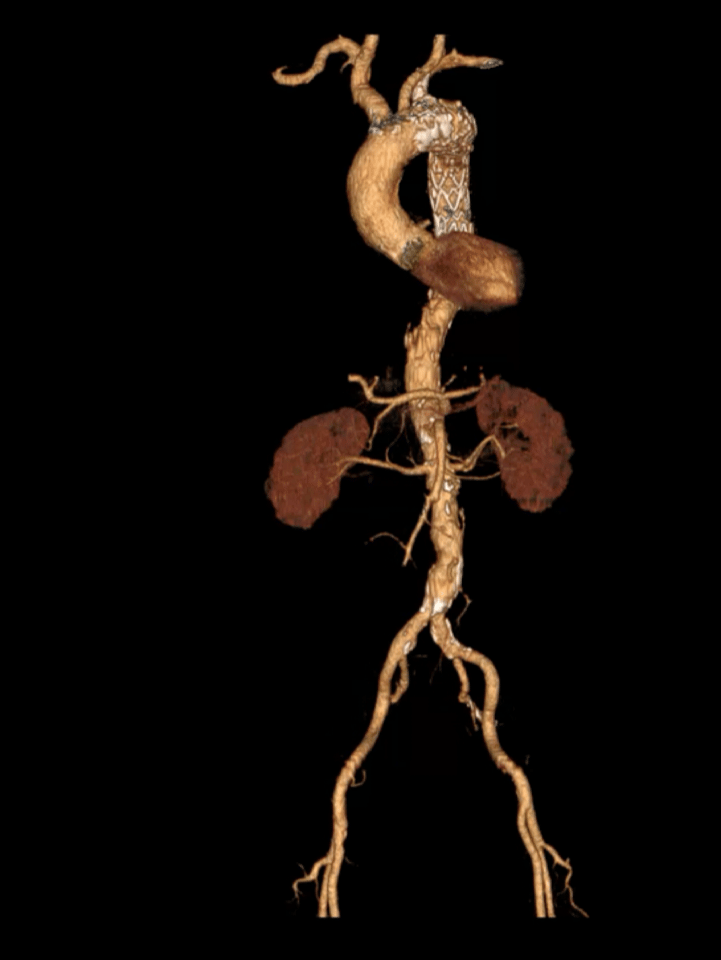

术前三维重建/CTA

术前CTA详解:

主动脉弓部动脉瘤,紧贴左锁骨下动脉开口,主动脉弓部大量附壁血栓。左颈总后缘处主动脉直径35mm,左锁骨下动脉前缘主动脉直径37mm,左锁骨下动脉后缘主动脉直径38mm,颈动脉后缘到瘤体中心线长度18mm,左颈总动脉距离左锁骨下动脉9mm。锁骨下动脉粗大,根部直径14mm*17mm。

患者于出院前行CTA检查,结果显示,动脉瘤隔绝良好,无内漏;分支支架通畅,形态良好;椎动脉供血良好。

术后三维重建/CTA